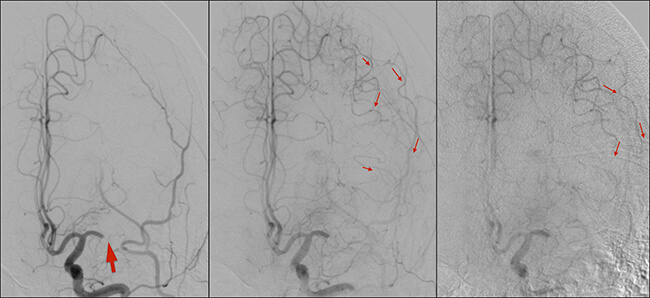

Αγγειογραφία: Προωθούμε μέσα από το μηριαίο θηκάρι, σύρμα και ευρύ οδηγό καθετήρα που έχει αποφρακτικό μπαλόνι στο περιφερικό άκρο του. Καθετηριάζουμε εκλεκτικά την αριστερή κοινή καρωτίδα στην πλευρά της αποφράξεως. Κάνουμε μία λήψη αγγειογραφίας με έγχυση σκιαγραφικού γιά να δούμε τον καρωτιδικό διχασμό και το σημείο της απόφραξης.

Βλέπουμε ότι ο θρόμβος έχει μετακινηθεί και αποφράσσει πλήρως την αριστερή μέση εγκεφαλική αρτηρία στο Μ1 τμήμα της (παχύ κόκκινο βέλος). Διακρίνουμε τα παράπλευρα αγγεία που διατηρούν βιώσιμη την περιοχή του εγκεφάλου που κινδυνεύει να νεκρωθεί (λεπτά κόκκινα βέλη).